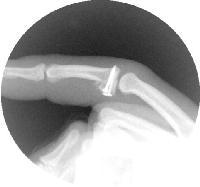

The pins are replaced with screws, one at a time. Here, two 1.3mm and one 1.0mm screws were used.

The last step before repairing the flexor tendon sheath is reattaching the volar plate. One method is to slightly back out the lateral screws, loop a suture from each corner of the volar plate around them, tighten and tie the suture, then advance the screws back in. The third screw provides extra security during this step.